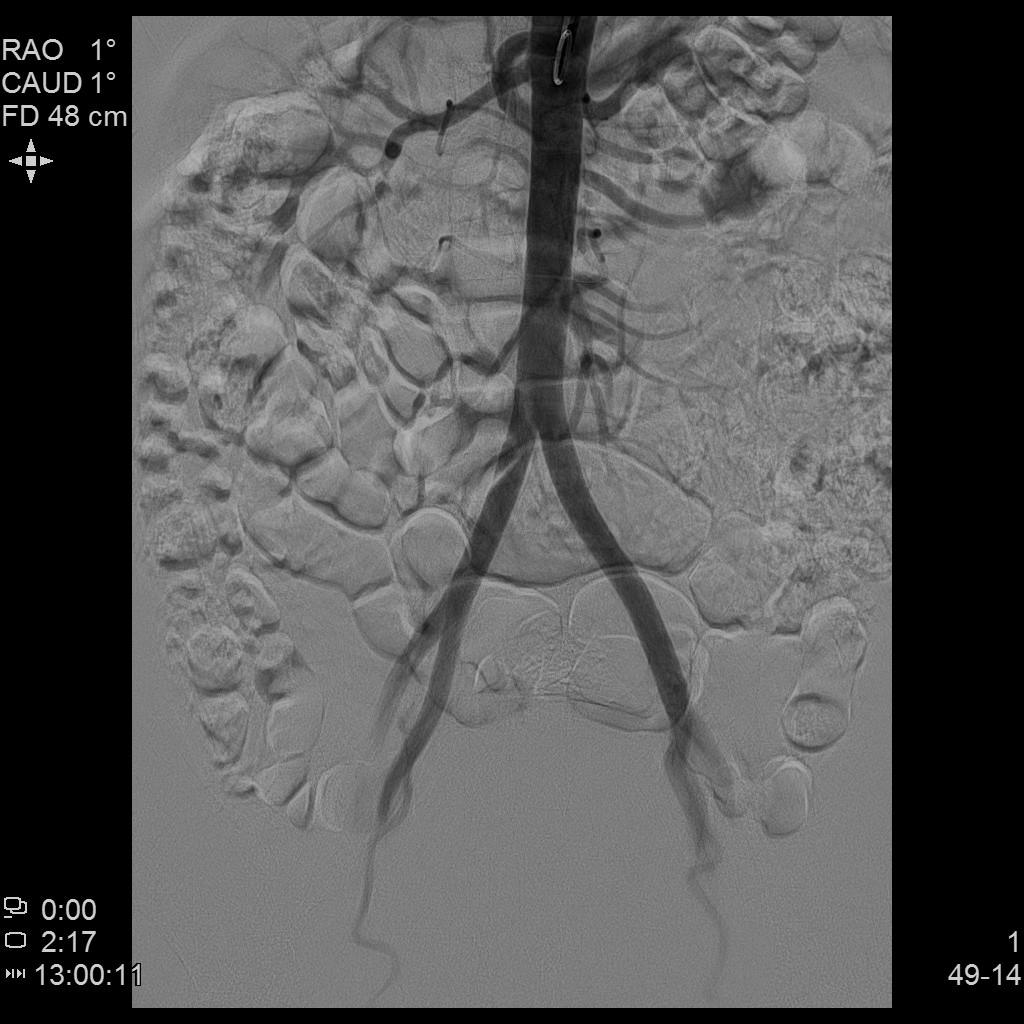

- 插管至右侧髂内动脉造影,显示右侧子宫动脉

腹主动脉造影